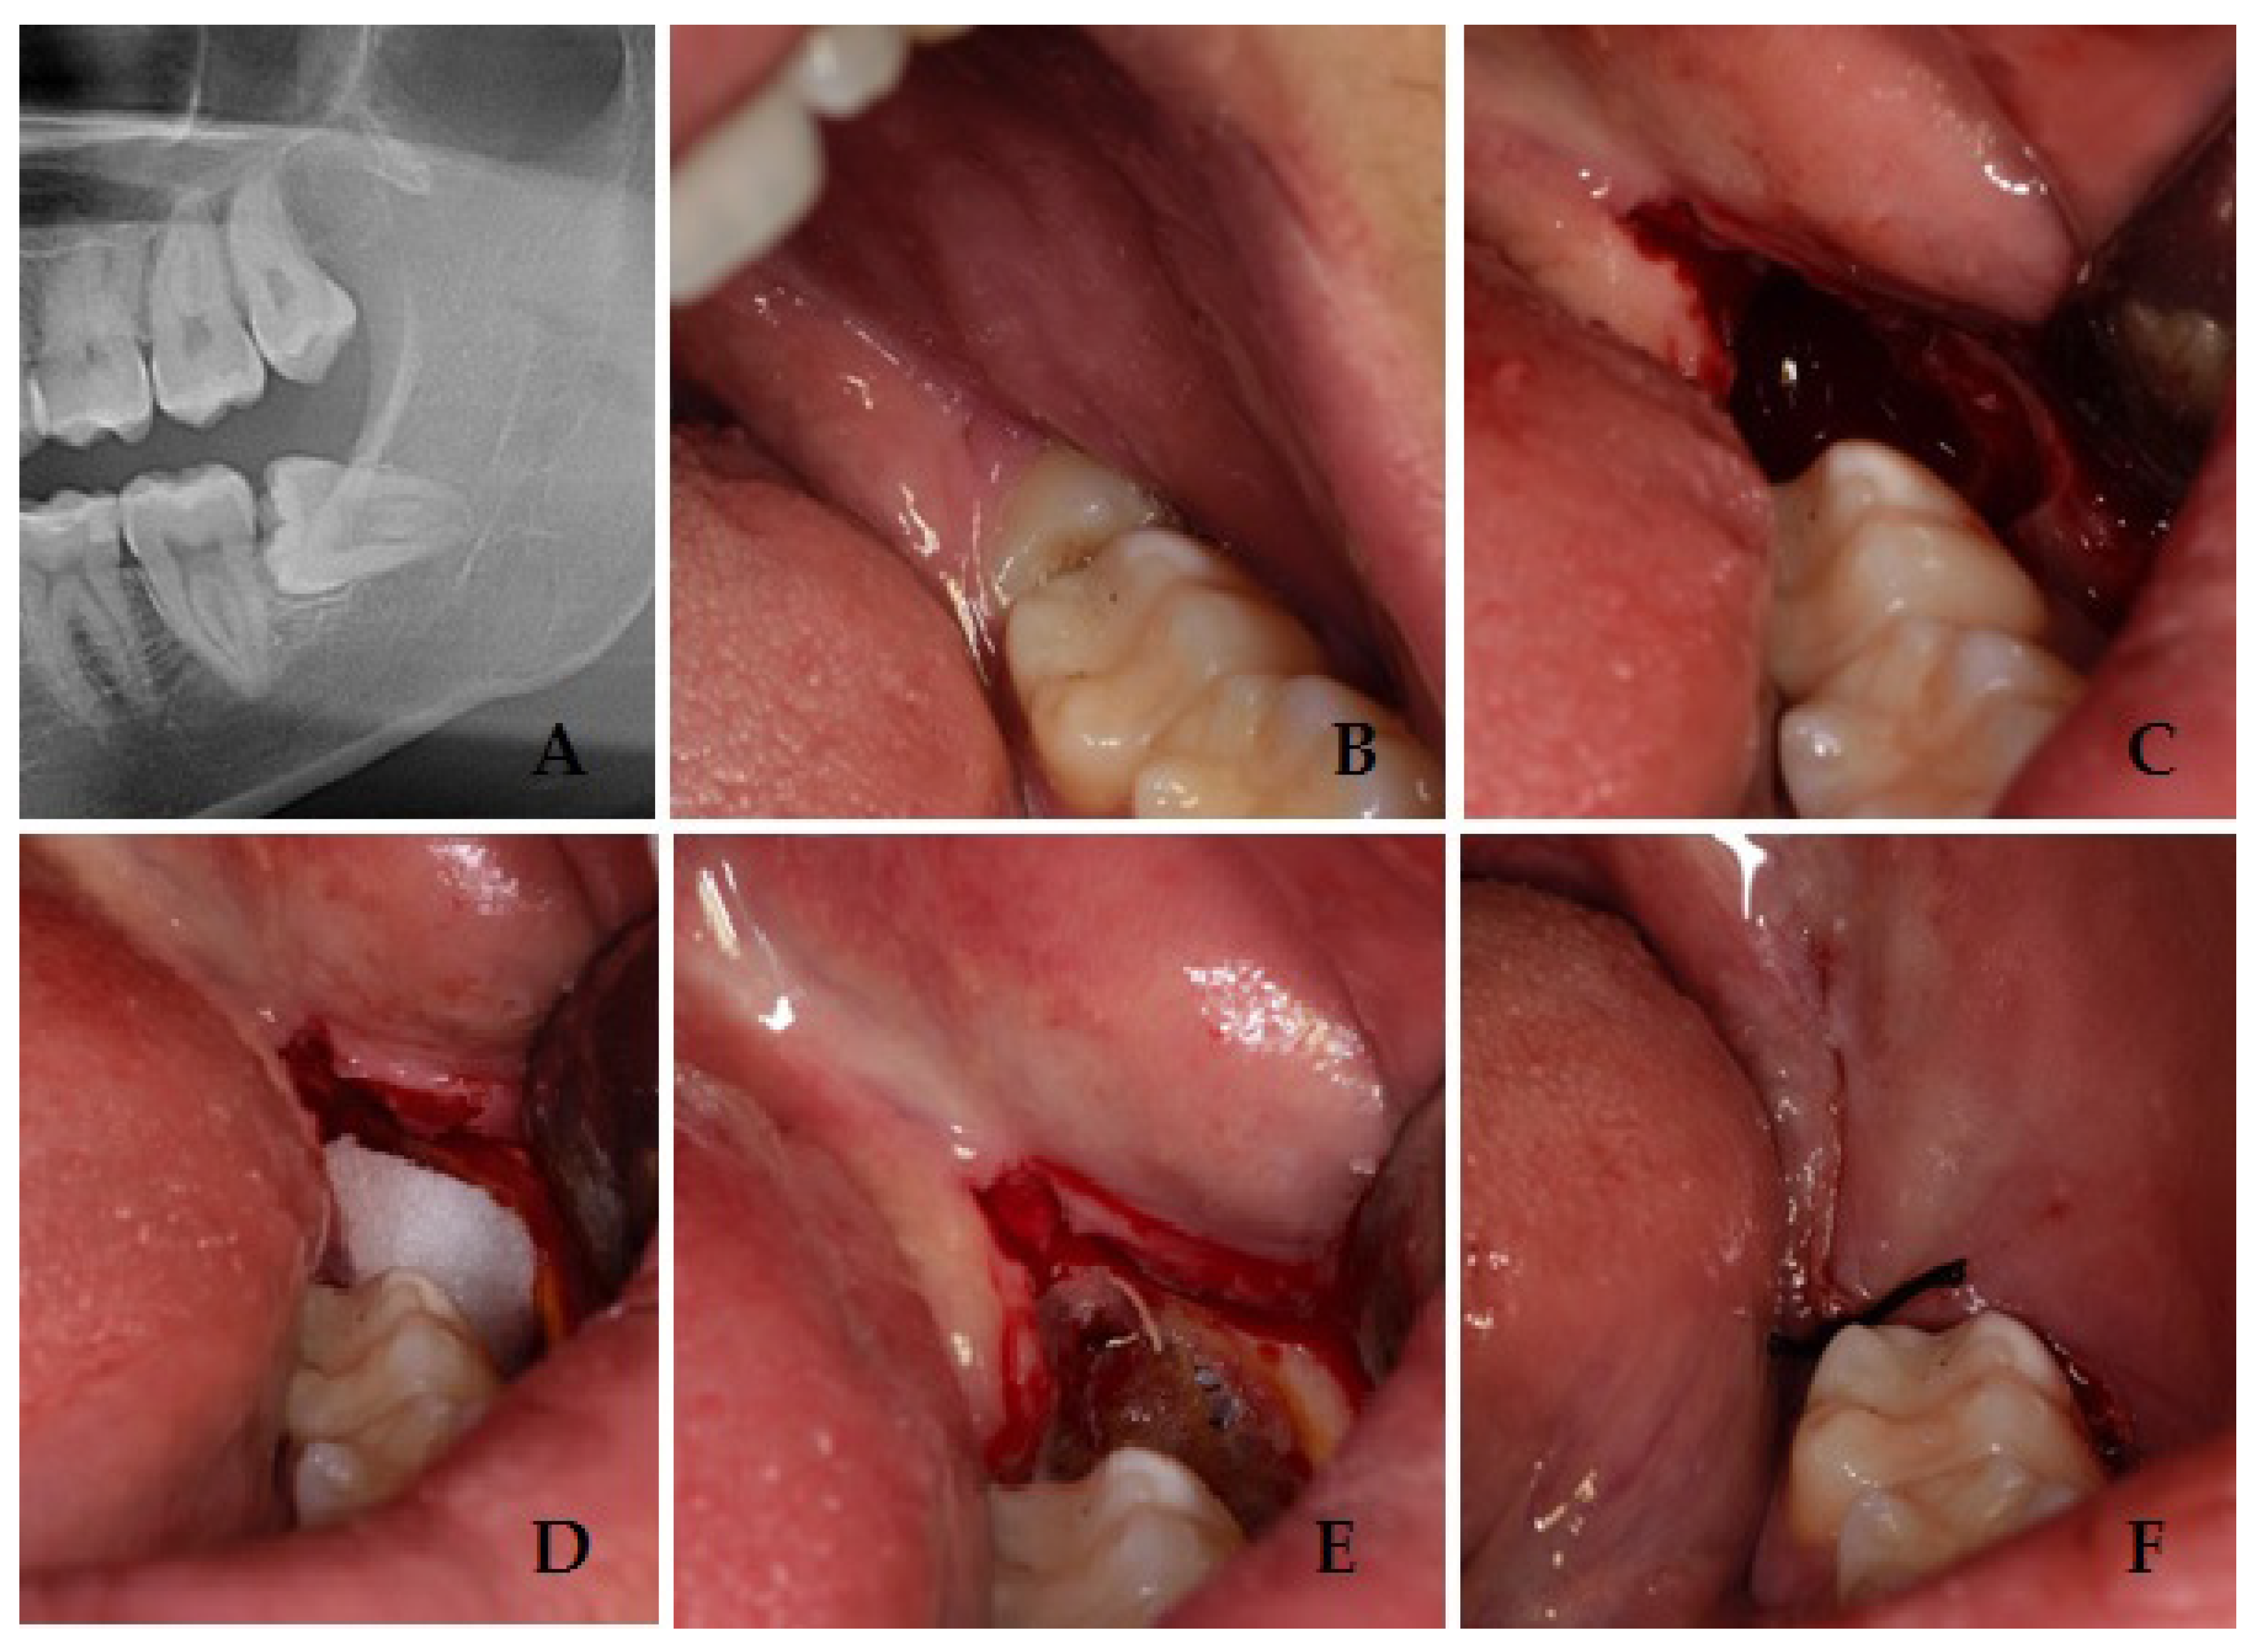

2. Materials and Methods